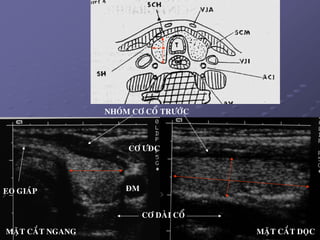

2. Giaûi phaãu SA:

 Lieân quan giaûi phaåu:

_ Cô.

_ Thöïc quaûn, khí quaûn, gai soáng.

_ 2 beân: maïch maùu vaø haïch coå.

9

EO GIAÙP

CÔ ÖÑC

ÑM

CÔ DAØI COÅ

NHOÙM CÔ COÅ TRÖÔÙC

MAËT CAÉT NGANG MAËT CAÉT DOÏC